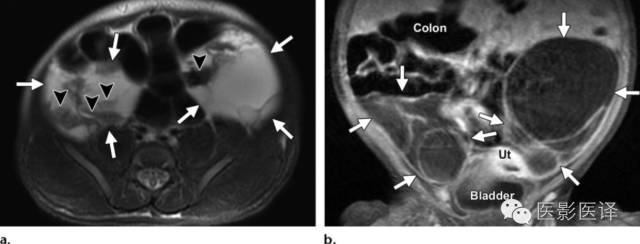

图5.双侧出血性新生儿卵巢囊肿。新生儿MR图像用于评估在外院胎儿超声中发现的两个实性腹内占位。(a)轴位脂肪饱和T2WI MR图像显示双侧多房的附件占位(a和b箭),伴有液液平面(箭头),提示出血。(b)冠状位脂肪饱和T1WI增强MR成像显示双侧占位无实性成分(箭)。多囊占位独立于结肠、肝脏、脾脏和肾脏,在膀胱上方。双侧病变均位于中线外侧。强化的子宫(Ut)在膀胱上方。

胎儿卵巢囊肿5.6厘米会消失吗,卵巢巨大囊肿与妊娠鉴别